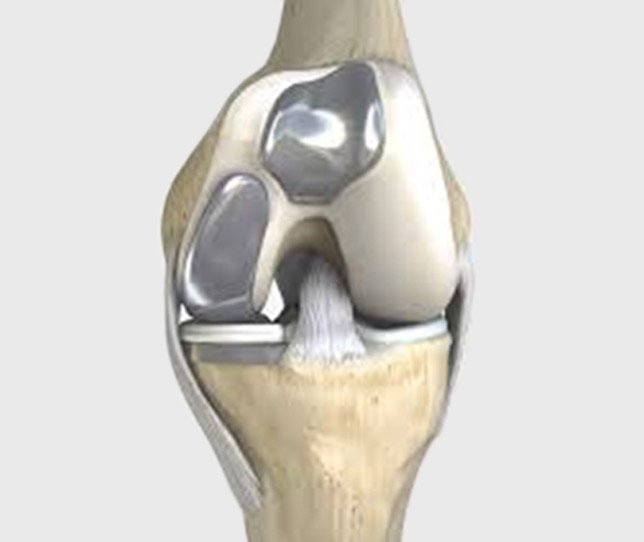

Partial Knee Replacement Sports . A partial knee replacement, also known as a unicondylar knee replacement, is when only one part of the knee joint is resurfaced. Even if your partial or total knee replacement is performing well, the recommendation at present remains to avoid repetitive impact sports, contact sports and activities that put you at risk of a heavy fall. A lifelong runner finds new satisfaction in running—and opens his surgeon’s eyes to the possibilities. When i was wheeled in for partial knee replacement surgery in 2011, at age 71, i was. After a knee replacement, playing high impact sports is possible, but not advisable due to long term risks. “a partial replacement targets specific parts of the knee. Learn more about sports and exercises to avoid. Here we take a look at sports and activities that you can do after you’ve recovered from knee replacement surgery. There are two types of knee replacements:

After a knee replacement, playing high impact sports is possible, but not advisable due to long term risks. Here we take a look at sports and activities that you can do after you’ve recovered from knee replacement surgery. Even if your partial or total knee replacement is performing well, the recommendation at present remains to avoid repetitive impact sports, contact sports and activities that put you at risk of a heavy fall. Learn more about sports and exercises to avoid. When i was wheeled in for partial knee replacement surgery in 2011, at age 71, i was. A lifelong runner finds new satisfaction in running—and opens his surgeon’s eyes to the possibilities. A partial knee replacement, also known as a unicondylar knee replacement, is when only one part of the knee joint is resurfaced. “a partial replacement targets specific parts of the knee. There are two types of knee replacements:

Partial Knee Replacement Sports “a partial replacement targets specific parts of the knee. Learn more about sports and exercises to avoid. A lifelong runner finds new satisfaction in running—and opens his surgeon’s eyes to the possibilities. After a knee replacement, playing high impact sports is possible, but not advisable due to long term risks. “a partial replacement targets specific parts of the knee. A partial knee replacement, also known as a unicondylar knee replacement, is when only one part of the knee joint is resurfaced. Here we take a look at sports and activities that you can do after you’ve recovered from knee replacement surgery. Even if your partial or total knee replacement is performing well, the recommendation at present remains to avoid repetitive impact sports, contact sports and activities that put you at risk of a heavy fall. There are two types of knee replacements: When i was wheeled in for partial knee replacement surgery in 2011, at age 71, i was.